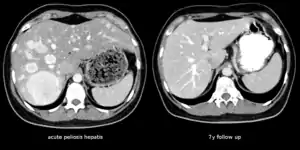

The CT scan of a patient with peliosis hepatis (left): The follow-up CT (right) after 7 years shows full remission.

Peliosis hepatis is an uncommon vascular condition characterised by multiple, randomly distributed, blood-filled cavities throughout the liver. The size of the cavities usually ranges between a few millimetres and 3 cm in diameter.[1] In the past, it was a mere histological curiosity occasionally found at autopsies, but has been increasingly recognised with wide-ranging conditions from AIDS to the use of anabolic steroids. It also occasionally affects spleen, lymph nodes, lungs, kidneys, adrenal glands, bone marrow, and other parts of gastrointestinal tract.[2]

Treatment is usually directed towards management of the underlying cause. Withdrawal of azathioprine leads to remission in kidney transplant; bacillary peliosis responds to antibiotics. In rare circumstances partial resection of liver or transplant may be required.